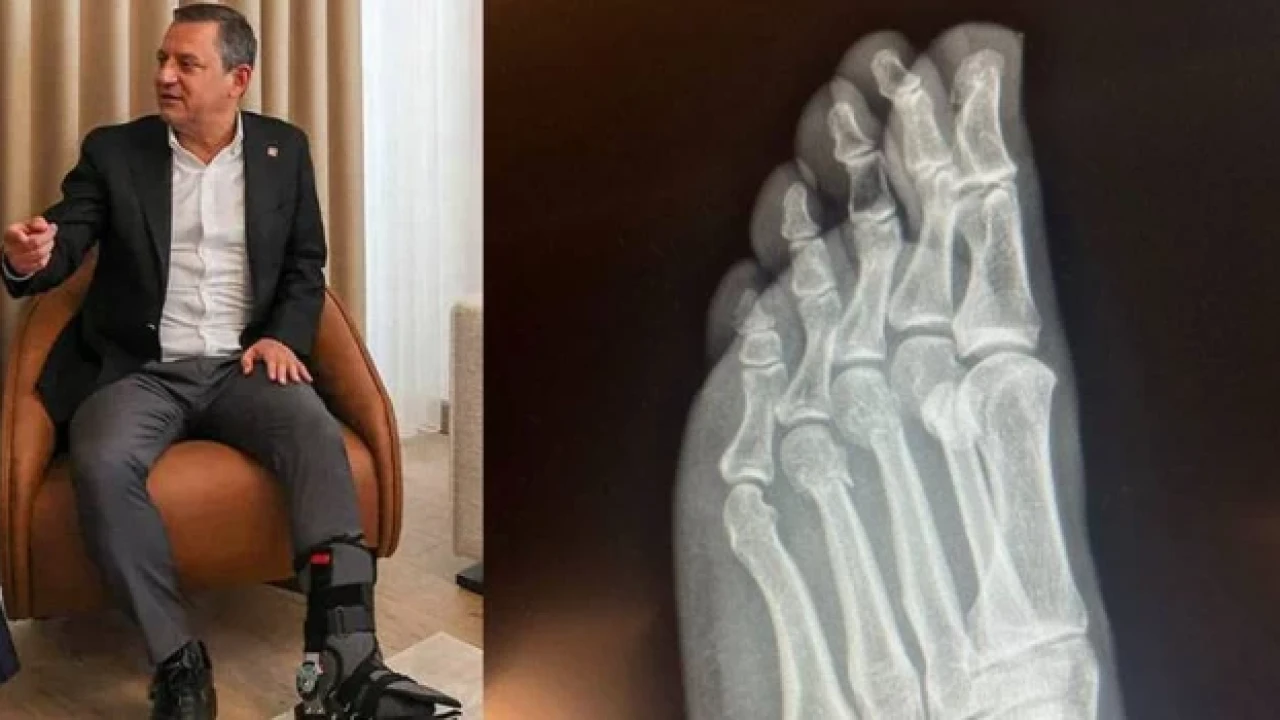

CHP Genel Başkanı Özgür Özel, “Herkes inceleyebilir” dediği filmleri de paylaştı. Ortopedist Prof.Dr. Tarık Yazar, filmleri inceleyerek değerlendirmede bulundu.

Prof. Yazar, şunları söyledi:

“Sayın Özgür Özel’in röntgen filmlerini incelediğimizde parmak kemiklerindeki kırıkları gördüm. Açık bir yara olmaması bir şanstır. Yani, dışarıya kan akmamış. Röntgende yara olup olmadığı her zaman görülmez. Ancak, Özgür Bey’in röntgenini incelediğimizde yine de şanslı olduğunu gördüm. Biz buna ‘şanslı kırık’ deriz. Aslında tam kırık da diyemeyiz. Ayrılmamış, kemiğin özelliği bozulmamış. İyileşme yeteneğinin fazla olduğu bir bölgede kırık var. Şanslı tarafı kanlanmanın kuvvetli olduğu bir bölgede kırık gördüm. Bilgisayarlı tomografiyle takibi uygun olur. Tedaviye doğru başlanmış. Mutlaka iyileşecektir. Kullandığı ayak desteği gayet doğru bir seçim. Üç aya kalmaz tam iyileşme gerçekleşir. Lütfen bir daha düşmesin.”